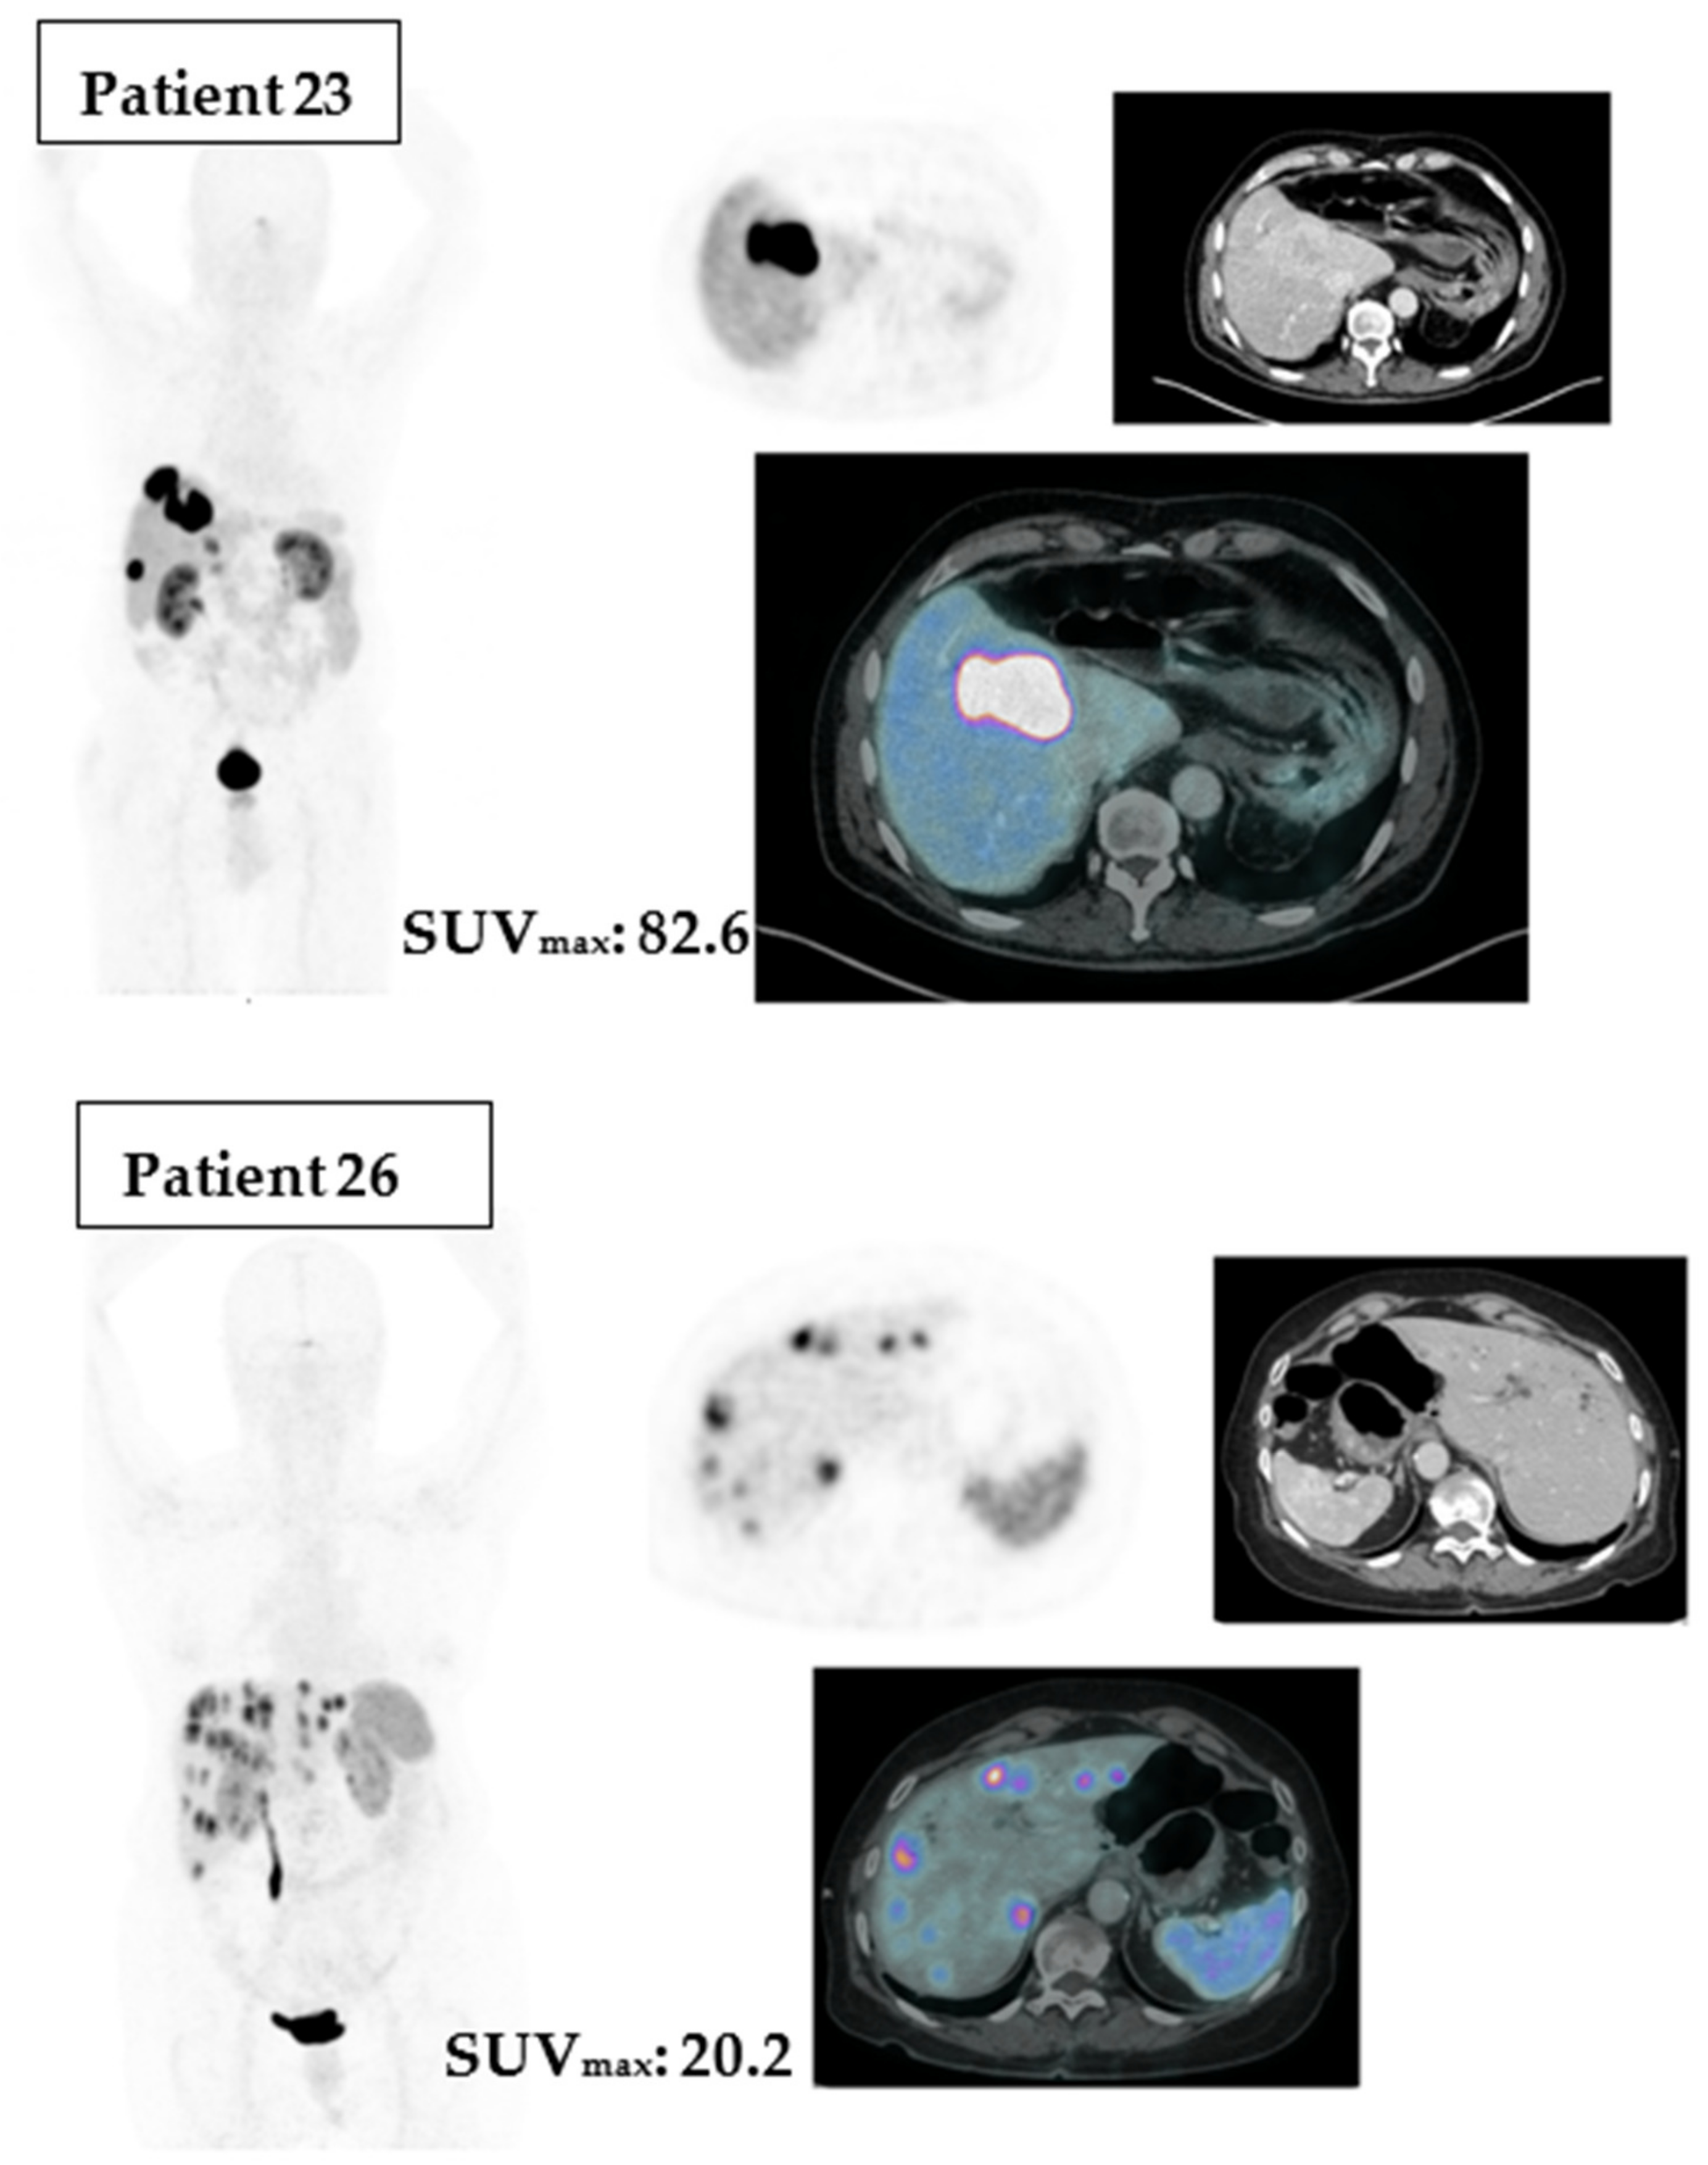

SUVmax was available for 34 patients. The estimated (or calculated) SUVmax cut point was 34.53. Patients holding an SUVmax above this value exhibited a statistical trend toward a longer median PFS (52.0 versus 18.7 months; p = 0.06), Figure 4. Unexpectedly, the lowest SUVmax (cut point 8.08) holds an inverse relationship with the median PFS (p = 0.0022). These findings suggest that certain nuclear features may be predictive of treatment response in this patient population.

To illustrate the differences between Ga-68 DOTA PET/CT SUVmax above or under the cut point, we point out two cases in Figure 5.

Due to a scarcity of predictors for PRRT treatment response, we turned back to pre-treatment Ga-68 DOTA PET/CT registered; after statistical analyses of their parameters, SUVmax was the most relevant of them. The cutoff of 34.53 established by the MSRS method on our sample showed that an SUVmax > 34.53 exhibited a statistical trend toward a longer PFS (p = 0.06). Our molecular imaging analyses also have limitations to disclose. Ga-68 DOTA PET/CT images were acquired after different injection periods, radiopharmaceuticals (Ga-68 DOTATOC and DOTATATE), and machines. Nevertheless, the SUVmax shows a promising predictor awaiting further data in prospective studies.